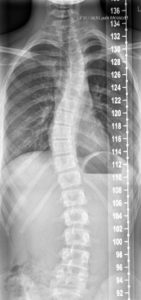

Durch jahrzehntelanger Erfahrung in der Behandlung von Wirbelsäulen können wir die Herstellung von fixierenden und stabilisierenden sowie wachstumslenkenden Rumpforthesen nach modernsten Kriterien gewährleisten.

Rumpforthesen werden eingesetzt, um die Wirbelsäule zu fixieren, zu korrigieren (Redression), aufzurichten (Reklination), zu entdrehen (Derotation) oder zu strecken (Extension). Unterschieden werden passive und aktive Rumpforthesen. Die passiven Rumpforthesen, auch Stützkorsetts genannt, werden zur Entlastung instabiler Wirbelsäulen eingesetzt, u.a. mit dem Ziel der Schmerzlinderung. Aktive Rumpforthesen sollen Fehlstellungen der Wirbelsäule korrigieren, wie sie bspw. als Folge von Erkrankungen wie Skoliose, Kyphose, Morbus Scheuermann, Hyperlordose und Osteoporose auftreten. Rumpforthesen werden bei Kindern und Jugendlichen eingesetzt, um das Wachstum zu lenken und Fehlstellungen zu korrigieren.